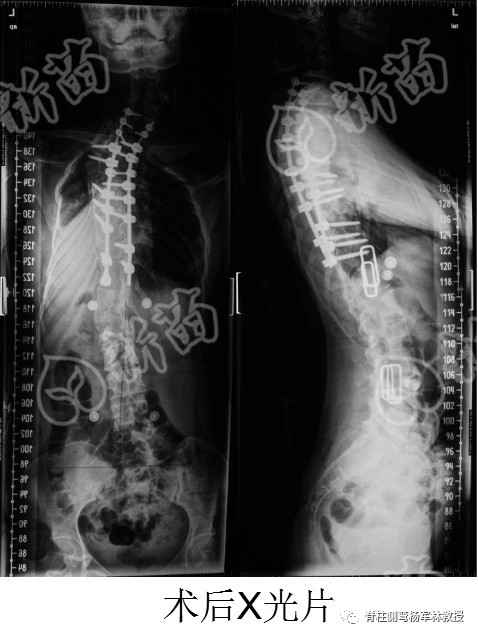

2013年6月28日的那场手术,历时十几个小时,医疗团队的精力与体力也高度透支。后来家人告诉我,我被推出手术室的时候,杨教授已经脸色发白,累到说不出话。

据说手术中有诸多危险情况,但战果颇丰——外观矫正,心肺功能明显好转,奇妙的是,我还长高了将近十厘米!

从此,我的人生分为两个阶段:手术前和手术后。